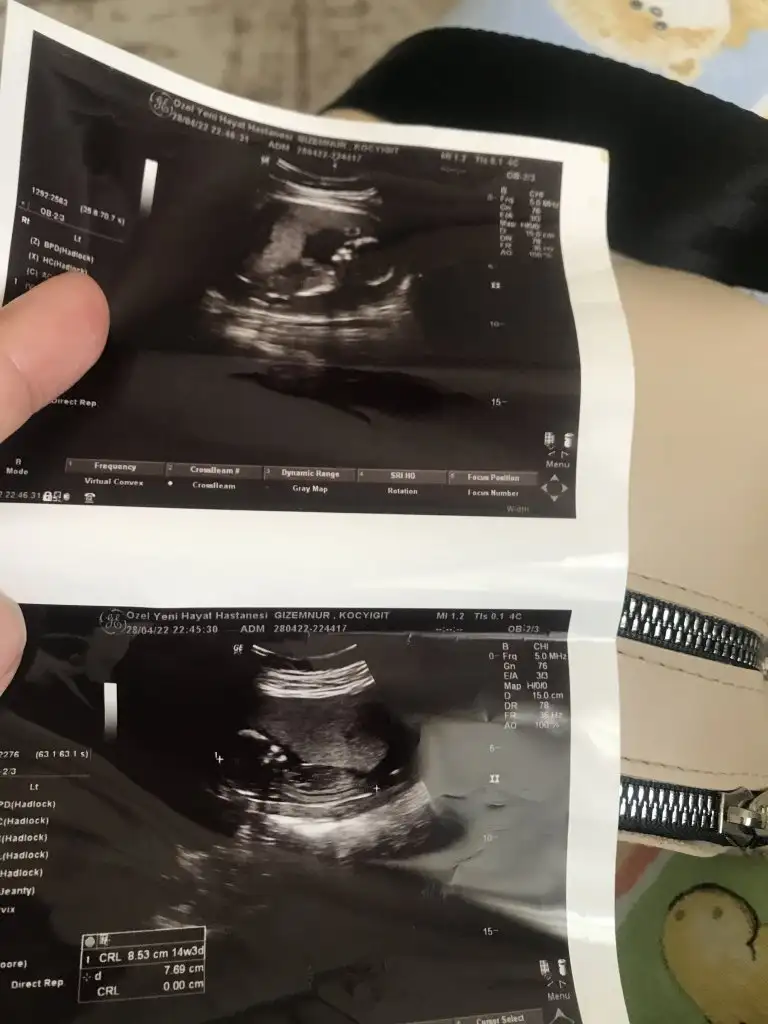

Bugün aslında çok güzel bi gündü bizim için sabah sevinçle kalkın bebeğimi 3 boyutlu görmek için bir kadın doğum doktorundan randevu almıştım cihazları çok iyi diye.

Randevu saatinde oradaydık doktor bebeğe baktı ve suyunun çok az olduğunu bebeğin haraketlerinin çok kısıtlı olduğunu söyledi. İnanamadım dalga geçiyo sandım dünyam başıma yıkıldı resmen eşimle şok geçirdik. Ordan çıktım ve doktorumu aradım ağlayarak hemen gel dedi. Gittim muayene etti bebeğin suyunda bi azalma var ama amacının 28. Haftalara kadar götürmek olduğunu yaşayabileceğini ama kalbininde durabileceğini söyledi. Yani şuan için her şey Allahtan…

İzmir’in en iyi perinatoloji doktoruna yönlendirdi hemen şuan sıra bekliyoruz. Ağladım ağladım rahatladım elimizden gelen ne varsa yapıp beklicez bebeğiniz için sizlerden dua istiyorum tek istediğim onu sağ Salim kucağıma almak.